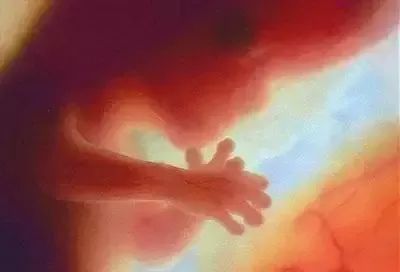

四个月:胎儿长度约13~17 cm,体重约125克。骨骼系统进一步发育,胎盘完全形成,胎儿肢体活动,母亲感觉胎儿运动,肌肉发达。虽然胎儿的毛发还没有出现,他的头皮结构已经开始发育。虽然他仍然闭上眼睛,他的眼球可以缓慢移动,甚至开始有长长的指甲。

五个月:艰难和幸福的诞生已经过去了一半。婴儿头上有长发,眉毛和睫毛长出来,身体的绒毛状长度覆盖整个身体;长度20~30厘米,体重250~300克;子宫内位置合适;如果耳朵靠近母亲的腹部,你可以听到他。胎儿的节拍;此时,有一层油腻的白色物质覆盖在心脏上。这种物质覆盖胎儿全身,被称为胎儿皮脂,它长期保护羊水中胎儿皮肤,并在生产过程中减少婴儿通过产道的阻力。